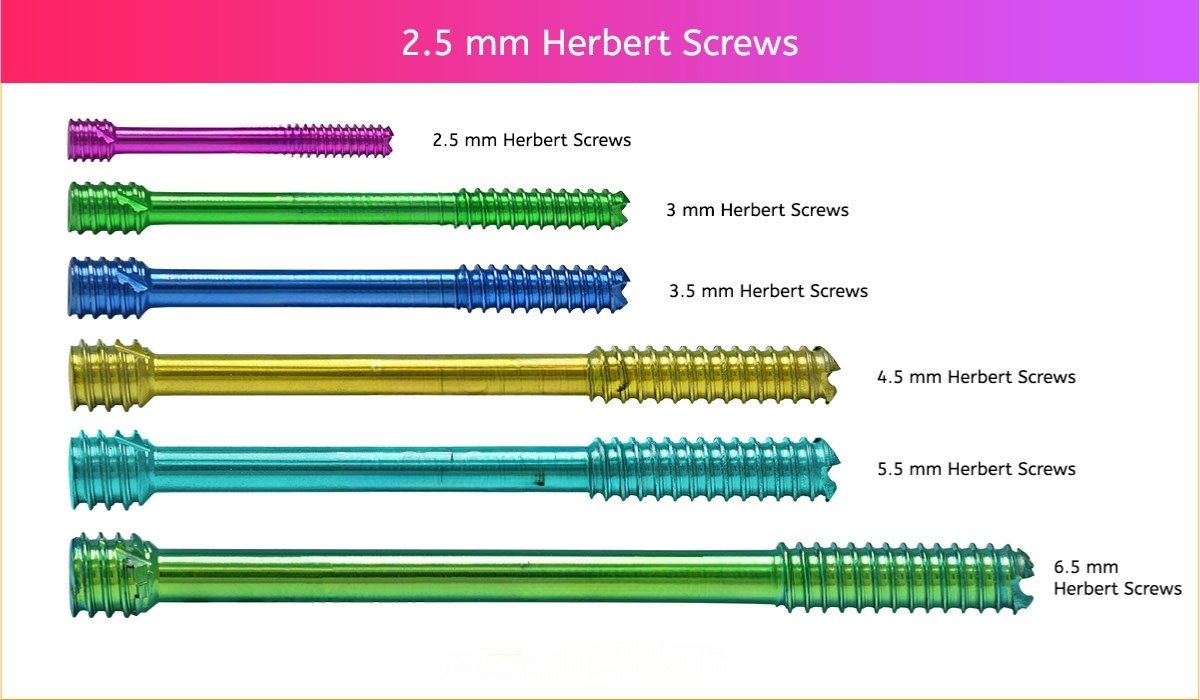

2.5 mm Herbert Screw

3 mm Herbert Screw

3.5 mm Herbert Screw

4.5 mm Herbert Screw

5.5 mm Herbert Screw

6.5 mm Herbert Screw

Herbert Screws Sizes

2.5 mm Screws Length

8mm, 10mm, 12mm, 14mm, 16mm, 18mm, 20mm, 22mm, 24mm, 26mm, 28mm and 30mm.

3 mm Screws Length

8mm, 10mm, 12mm, 14mm, 16mm, 18mm, 20mm, 22mm, 24mm, 26mm, 28mm and 30mm.

3.5 mm Screws Length

8mm, 10mm, 12mm, 14mm, 16mm, 18mm, 20mm, 22mm, 24mm, 26mm, 28mm, 30mm, 32mm, 34mm, 36mm, 38mm, 40mm, 42mm, 44mm, 46mm, 48mm, 50mm, 55mm, 60mm, 65mm, 70mm, 75mm and 80mm.

4.5 mm Screws Length

8mm, 10mm, 12mm, 14mm, 16mm, 18mm, 20mm, 22mm, 24mm, 26mm, 28mm, 30mm, 32mm, 34mm, 36mm, 38mm, 40mm, 42mm, 44mm, 46mm, 48mm, 50mm, 55mm, 60mm, 65mm, 70mm, 75mm and 80mm.

5.5 mm Screws Length

12mm, 14mm, 16mm, 18mm, 20mm, 22mm, 24mm, 26mm, 28mm, 30mm, 32mm, 34mm, 36mm, 38mm, 40mm, 42mm, 44mm, 46mm, 48mm, 50mm, 55mm, 60mm, 65mm, 70mm, 75mm, 80mm, 85mm, 90mm, 95mm, 100mm, 105mm, 110mm, 115mm and 120mm.

6.5 mm Screws Length

12mm, 14mm, 16mm, 18mm, 20mm, 22mm, 24mm, 26mm, 28mm, 30mm, 32mm, 34mm, 36mm, 38mm, 40mm, 42mm, 44mm, 46mm, 48mm, 50mm, 55mm, 60mm, 65mm, 70mm, 75mm, 80mm, 85mm, 90mm, 95mm, 100mm, 105mm, 110mm, 115mm and 120mm.